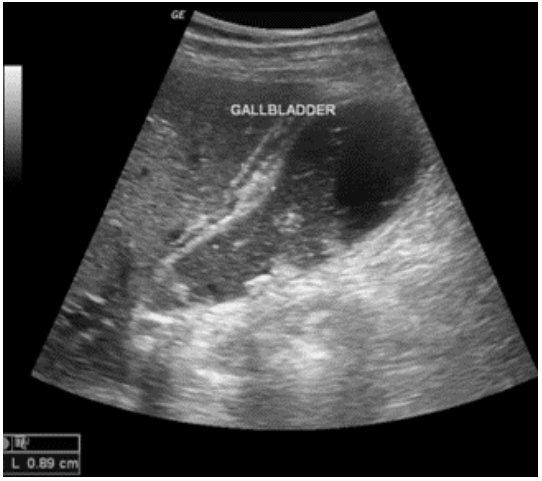

Paciente do sexo feminino, 69 anos, procurou atendimento de urgência referindo, há 1 dia, dor

abdominal em faixa superior, febre, náuseas e vômitos. Ao exame físico: dor a palpação do

hipocôndrio direito. Leucocitose. Evoluiu sem melhora do quadro clínico após analgesia.

Qual o diagnóstico mais provável?

Qual o diagnóstico mais provável?